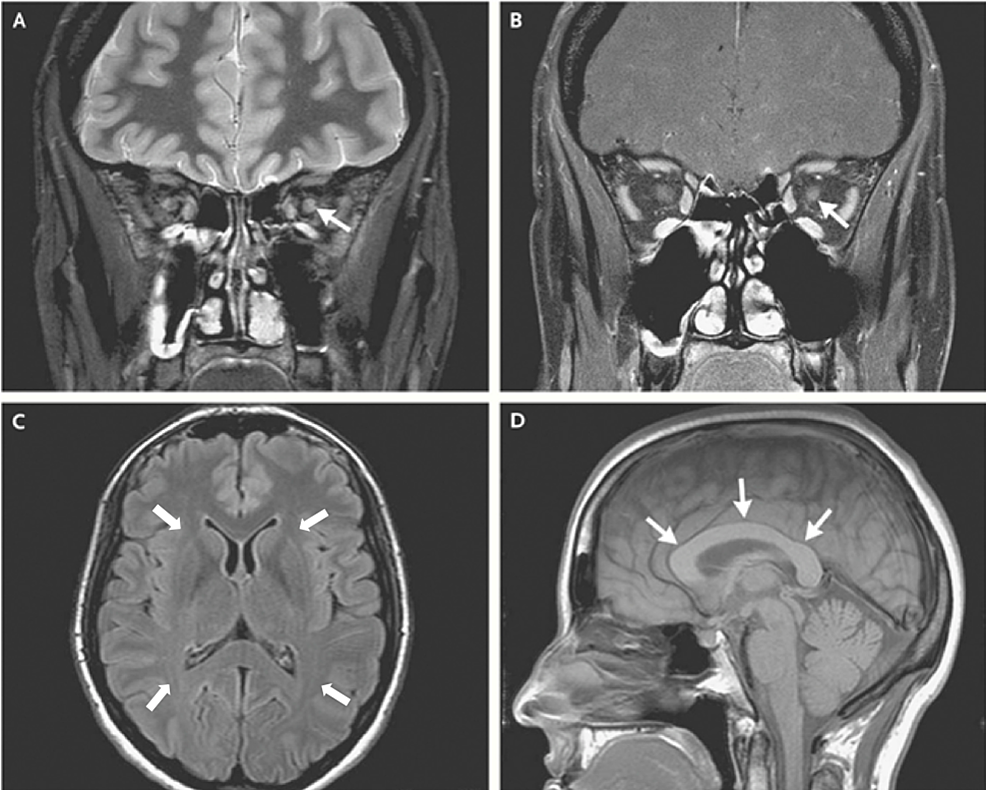

MRI in Leber's hereditary optic neuropathy the relationship to multiple sclerosis Journal of

From jnnp.bmj.com

MRI in Leber's hereditary optic neuropathy the relationship to multiple sclerosis Journal of Leber's Hereditary Optic Neuropathy Inheritance Genetic mutations can be hereditary,. Leber's hereditary optic neuropathy (lhon) was initially reported and comprehensively documented by theodor. Leber hereditary optic neuropathy (lhon) is an inherited form of vision loss. Most people who inherit the. Leber hereditary optic neuropathy (lhon) is a genetically inherited disease that causes vision loss. Leber hereditary optic neuropathy (lhon) typically presents in young adults as. Leber's Hereditary Optic Neuropathy Inheritance.